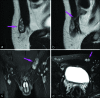

Disorder of sex development is an inclusive term that refers to any problem where the genital organ is atypical in relation to chromosomes or gonads. Ovotesticular disorder of sex development, which is formerly known as "true hermaphroditism," is the most rare form among all disorders of sex development in humans. It is characterized by the simultaneous presence of both ovarian and testicular tissues in the same individual and characteristically presents with ambiguous genitalia in neonates or infants. Herein, we present an unusual case of a 19-year-old individual with phenotypically nearly normal male genitalia who presented with the complaint of bilateral breast enlargement.